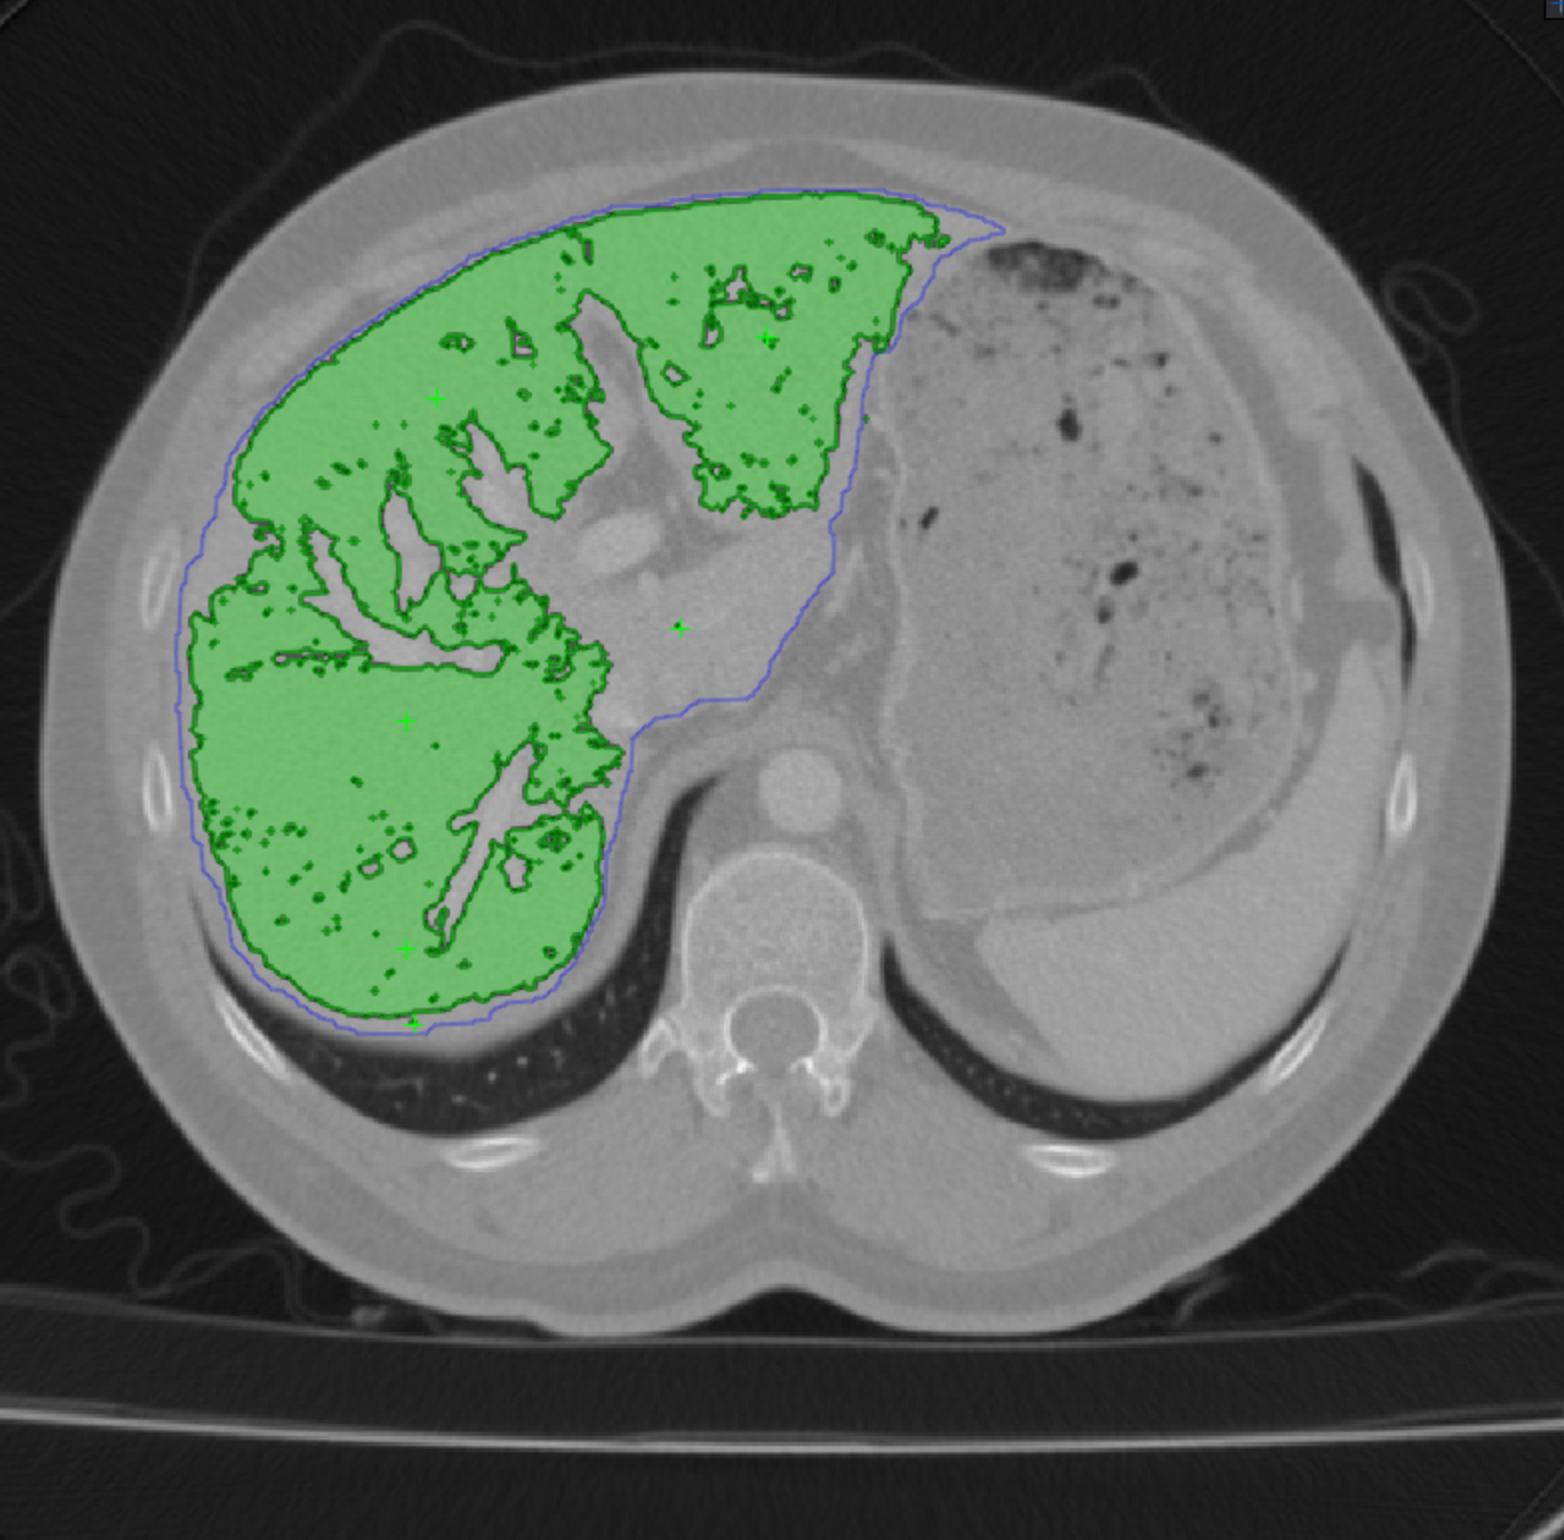

Minimizing during training ensures that the segmentations will be roughly correct. However, because the template can only be expected to provide a coarse depiction of the object, this is not enough. We therefore also minimize to force the network to yield accurate boundaries. Fig. 8 illustrates the influence of the and parameters on a real image. In practice, the results are insensitive to how they are chosen over a wide range. However, minimizing alone (=0) produces boundaries in that are exactly those of the template while minimizing alone (=1000) yields boundaries that exist in the image but are not necessarily those we are looking for. Minimizing a properly weighted sum of the two yields segmentations that conform to the template while matching actual image boundaries.

The template of Eq. 1 should approximately match the target structure. Hence, the annotator should supply points that are distributed across the object surface. These points are then used to deform the template. In practice, For structures of genus 0, we start from a simple spherical template but more complex ones are possible. As we increase the number of points, we get increasingly refined templates, as shown in Fig. 4.

To perform this deformation interactively, we developed a GUI that relies on Active Surface Models (ASMs) [26] implemented as a MITK [28] plugin. It lets the annotator supply a few points by clicking on 2D cross sections of the input image volume. The ASM then deforms the template in real-time and overlays it on the image data, both as 2D cross sections and 3D surface renderings. The annotator can then add more points wherever the deformed template is too far from the target organ’s boundary and iterate as often as necessary. This effectively puts the human in the loop in a painless and practical way. We illustrate this in a video that can be found in the supp. material.